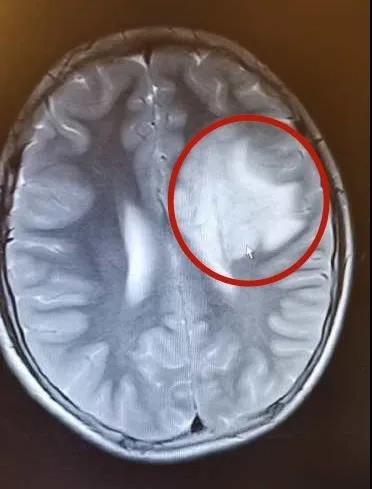

入院后再次复查的头颅MRI,结果仍然令人忧心——左侧额叶基底节有明显的占位性病变。从影像学分析,医生认为真真的疾病非常像是生殖细胞瘤,不能排除胶质瘤。

在使用了2个疗程的糖皮质激素后,真真的临床症状完全消失了,复查头颅MRI也有了惊喜的结果——原本非常大的脑部“肿瘤”奇迹般地开始消退了。

真真治疗前(左图)后(右图)的头颅MRI

巨大的占位性病变奇迹消退了